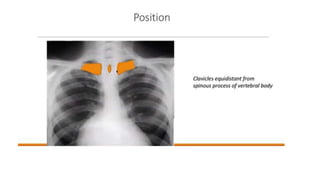

Chest x-ray in Congenital Heart disease

Chest x-ray inCongenital Heart disease